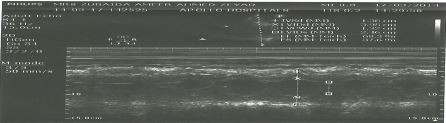

Chest x-ray showed mild cardiomegaly with both lung fields clear, while ECG was normal and cardiac stress test showed no significant cardiac lesion, whereas 2D echo with color Doppler showed concentric hypertrophy of the left ventricle with normal function (see Figure 4).

Figure 4: Echo showing concentric left ventricular hypertrophy

Figure 4: Echo showing concentric left ventricular hypertrophy